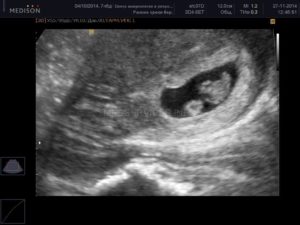

Узи двойни при беременности: фото на ранних сроках в 5-6 недель и позже

Определение двойняшек и близнецов осуществляется таким продуктивным методом исследования, как УЗИ. Этот вид обследования обеспечивает информацией о месте расположения ребенка, имеется ли многоплодная беременность и др.

Как правило, двое эмбрионов четко определяют на УЗИ с самых ранних недель — 5-7. Позже врач способен это определить и без применения ультразвуковой диагностики. Двойняшек можно выявить по такому признаку, как увеличенный размер матки, уже с ранних сроков, а медицинская диагностика с применением ультразвука покажет двух детей только на 1 скрининге — в 10-14 недель.

Двойняшки покажутся на УЗИ уже с 5 недели

Следовательно, наличие двойняшек в утробе выявляется посредством ультразвука уже через месяц после зачатия, на снимке они выглядят как 2 образования темного цвета внутри полости матки (см. фото УЗИ-обследования двойни ниже).

Увидеть двойню на УЗИ при беременности можно уже через месяц после зачатия. В этом случае специалист отметит на экране монитора два пятна черного цвета, которые хорошо просматриваются ультразвуком